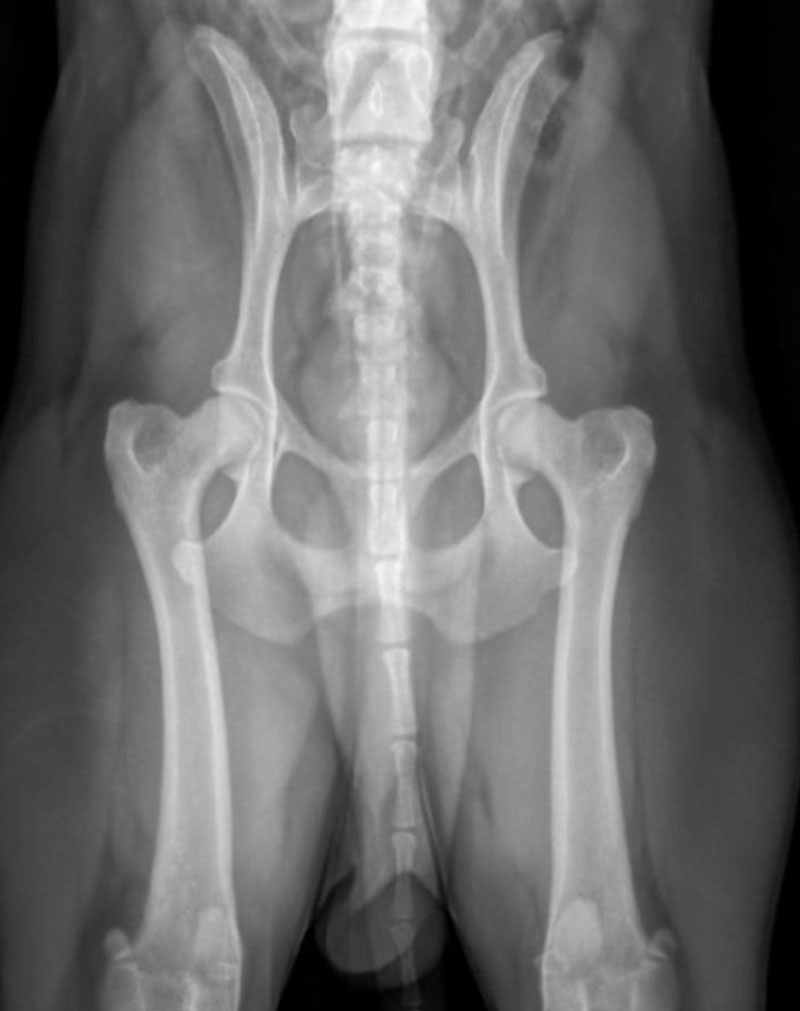

We are proud to offer state of the art Idexx radiology technology and equipment, which allows the clearest of images to be provided to our clientele. This is especially helpful when needing to determine final puppy count prior to whelp. The best time to perform a pregnancy radiograph is 55 days or later from breeding. An appointment is required for this service.

We are also proud to offer OFA (Orthopedic Foundation for Animals) image submissions. This is a requirement amongst many AKC breed clubs and may include several different image types such as:

We frequently receive inquiries regarding our success with proper positioning for OFA images, specifically for hips. Translating this success can be challenging, so we have included images of various breeds that we have taken. We take great pride in our success with these images and many others like them. As extreme perfectionists, we appreciate owners who understand that we strive for the best technique and outcome while minimizing stress and ensuring the comfort of your dog(s), particularly since all images taken here are done WITHOUT sedation.